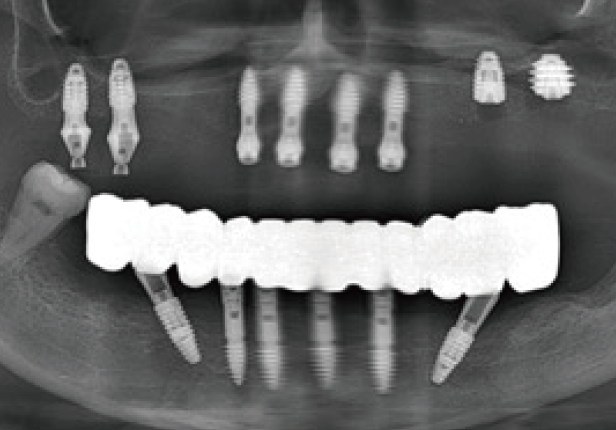

Maxilla Full Case Full case

Pre-surgery panorama

Post-surgery panorama

Final Crown Panorama